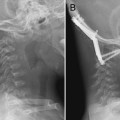

Figure 1–2 Sagittal magnetic resonance imaging showing the posterior longitudinal ligament (arrow) and the anterior longitudinal ligament (arrowhead).